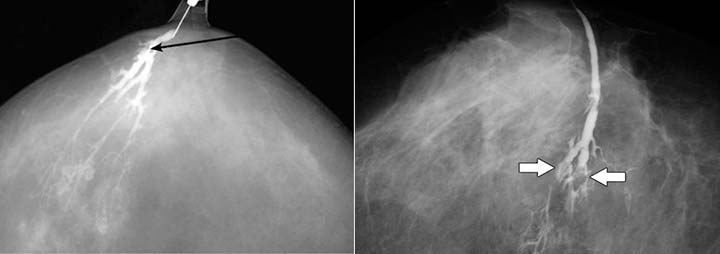

Выявить локализацию процесса помогает дуктография. Это рентгенологический метод диагностики, при котором в млечные протоки вводится контрастное вещество. Она назначается при патологических выделениях из грудных желез, но не во всех случаях. Нет показаний для проведения дуктографии если:

Специальная подготовка к дуктографии не требуется. Женщину нужно предупредить, что выдавливать кровь из соска перед процедурой нельзя. Обследование занимает около 30 минут. Специальным инструментом в протоки водится тонкий катетер, по которому нагнетается рентгеноконтрастный раствор. После этого выполняется стандартный снимок, как при маммографии.

Результат снимка оценивается в тот же день. Обычно внутрипротоковая папиллома не позволяет пройти раствору в дистальные отделы протока, поэтому на снимке появляется дефект наполнения. Дуктография — это безопасный метод диагностики патологии млечных протоков. Он безболезненный, но некоторые пациентки ощущают дискомфорт. По результатам исследования врач получает точное представление о локализации патологического образования, чтобы взять образец тканей для гистологической диагностики [5].

- Дуктография. Исследование представляет собой вид маммографии, при котором применяется контрастное вещество. Дуктография позволяет изучить протоки. На снимках врач увидит наросты, их размеры, локализацию и состояние образования.